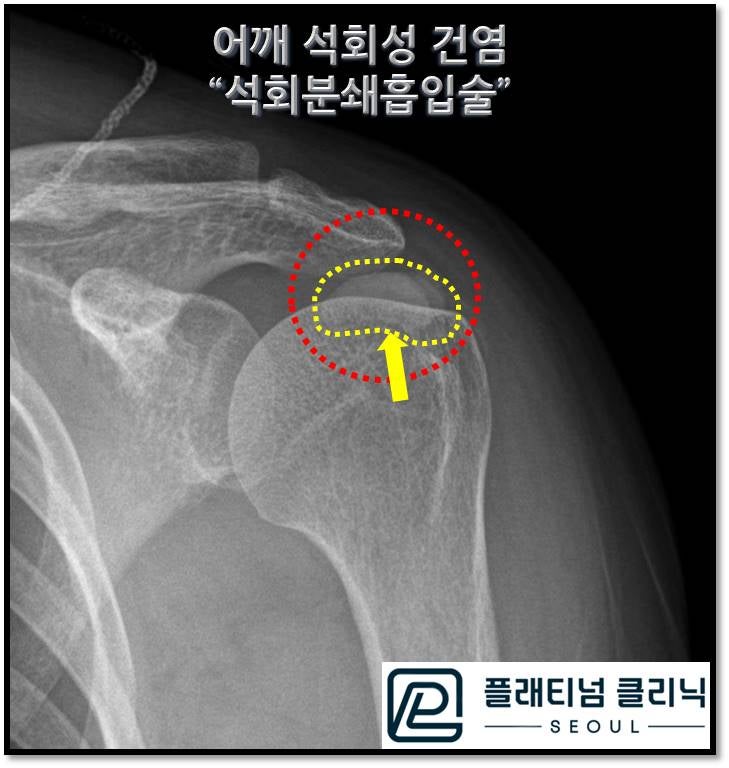

X-ray를 보면 빨간 원 안에 노란점선으로 표시된 부위가 하얗게 보이는데 이것이 석회입니다. 엄청 큰 석회가 있는 것이 확인됩니다. 초음파를 통해 석회의 정확한 크기와 양상, 위치를 확인하였습니다.

초음파상 약 2.10*1.82cm 크기의 거대한 석회가 관찰되며 위치는 극상근의 전체를 거의 덮고 있을 정도로 큰 석회로 관찰됩니다. 석회의 양상은 단단한 석회와 찐득한 석회가 공존해 있는 것으로 판단됩니다. 석회분쇄흡입술을 통해 석회를 제거하였습니다. 시술 후 주사기 사진을 보여드리겠습니다.